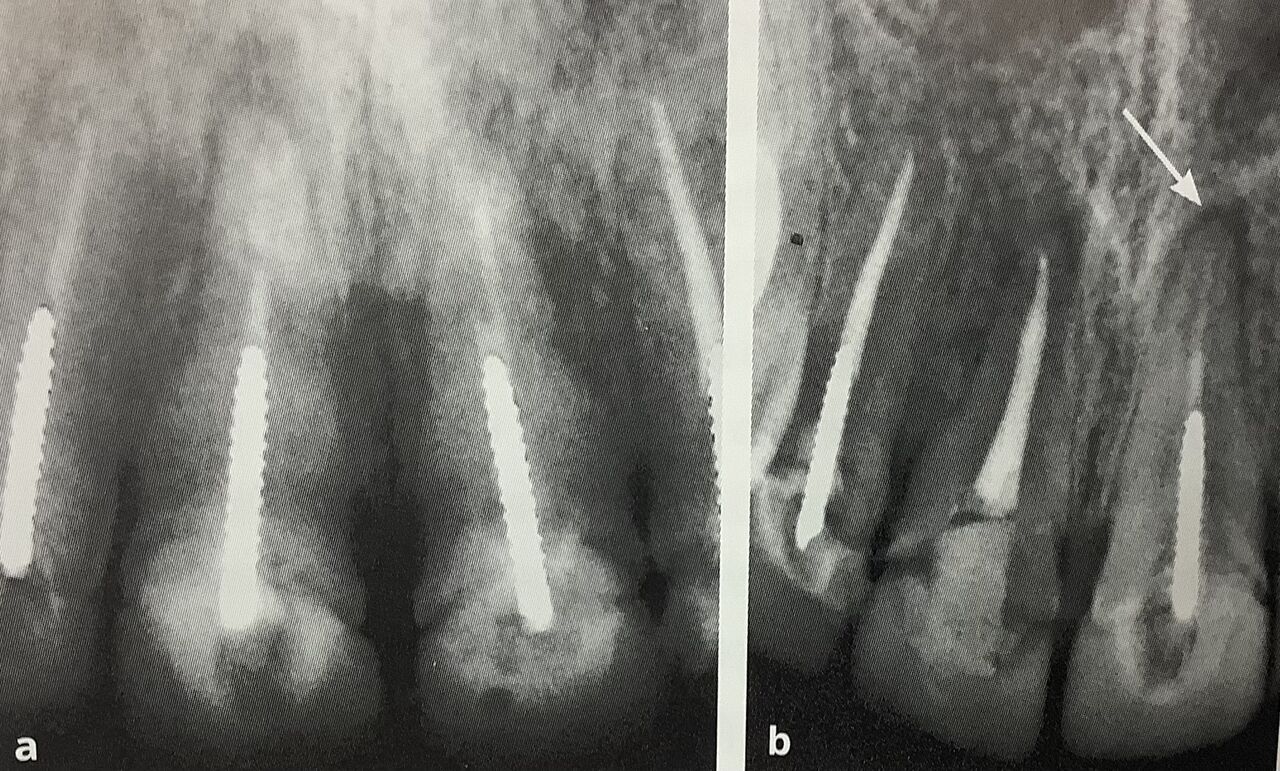

レントゲンでの右の真ん中の歯、

一番は随分と前に根管治療をされて何ともなかったそうですが、

新しく被せて直ぐに痛みが出てきました。

右が被せて6ヶ月後ものです。

矢印部分にハッキリとしカゲが有りますね左の治療前では鼻が重なっているので、白っぽくて見え難いからでは?